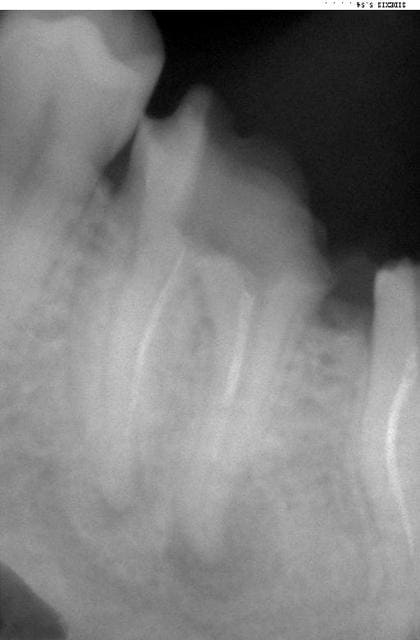

la Bio du jour à reprendre à 19h34 (fais chier)

Patient de 25 ans

Bienvenue chez les bisounours et les bien pensants. La 46 exposée plus haut,pas si mal traitée apparemment, vous en faites quoi, les sages et conquistadors de la dentisterie?